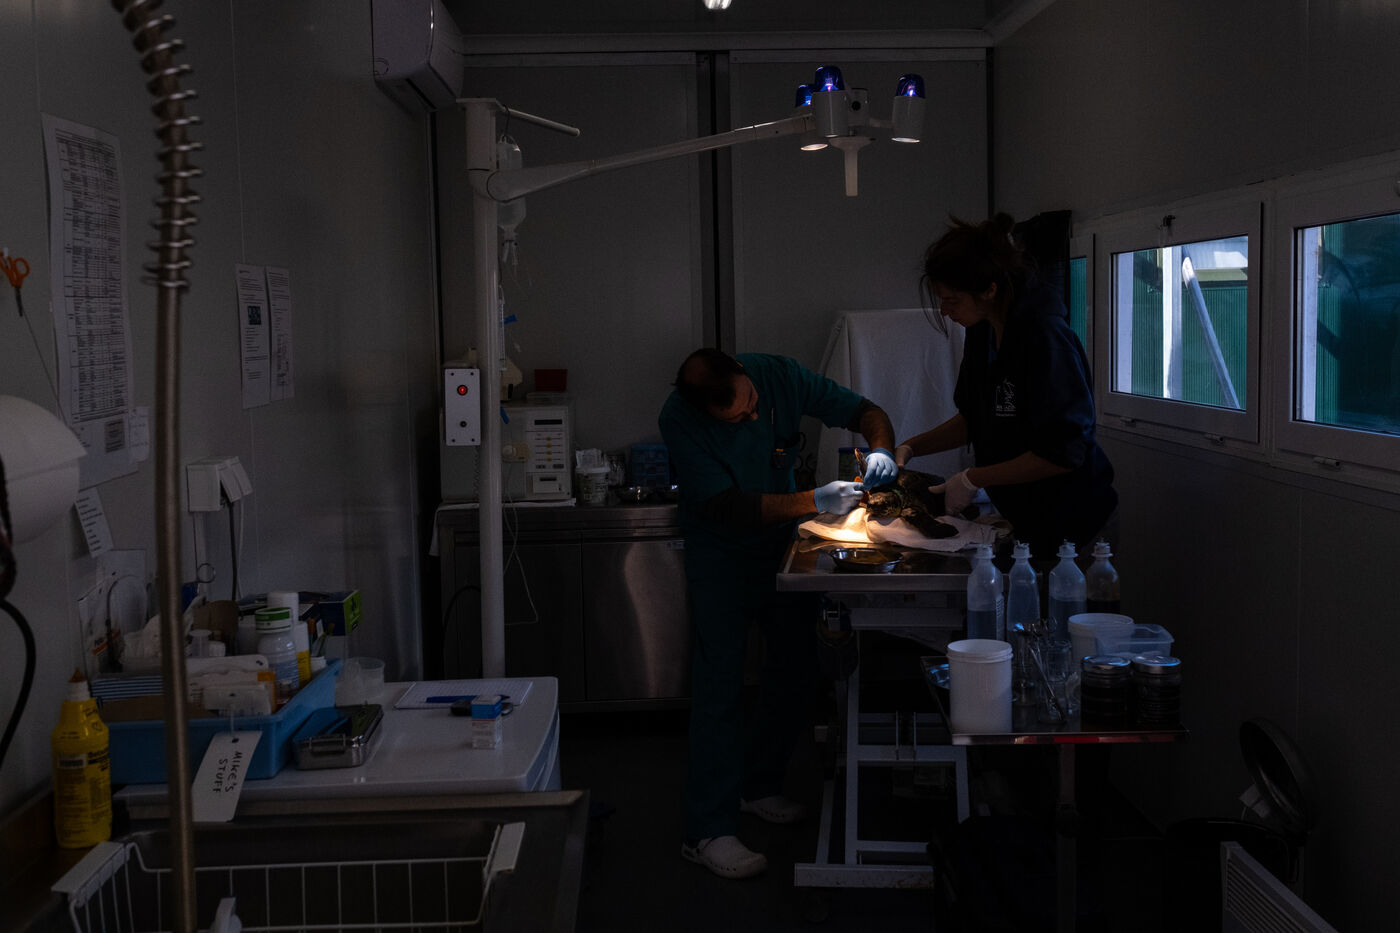

Les vétérinaires veillent aussi de près sur les tortues. Ils passent effectuer des relevés ou encore installer une perfusion. Parfois, ils emmènent une tortue dans le bloc opératoire pour des interventions plus complexe. Les tortues doivent parfois être amputés d'une ou plusieurs nageoires. « Malgré cela, elles peuvent souvent retourner dans la nature, ce sont des animaux puissants. » nous dit la biologiste. Des poids sont souvent fixés sur les carapaces des tortues. Les blessures à la tête causant des troubles neurologiques, l'installation de plaques de métal lestées leur aident à retrouver l'équilibre et à nager de nouveau.

Léa, une toute petite tortue Caouanne de 3 ans, a été trouvée sur la côte à proximité du centre par Alex, volontaire franco-canadien, qui a plongé pour aller la sauver. Elle présente des blessures sérieuses au cou et à la nageoire dues à un emmêlement dans un filet de pêche. « De plus, après avoir effectué une radiographie, nous nous sommes aperçus qu'elle a également ingéré un hameçon de pêche. » explique Alex. Eirini détaille son traitement ; « piqûres d'antibiotiques, de vitamines ainsi que le nettoyage des plaies. Malheureusement, sa nageoire est gravement endommagée, elle va devoir être amputée mais avant cela nous devons lui enlever l'hameçon qui est dans son estomac quand elle aura repris des forces. En attendant, elle a une perfusion de fluides car elle ne se nourrit pas. On ne peut pas savoir le temps dont elle va avoir besoin pour se rétablir, sûrement 4 ou 5 mois. Nous ne sommes pas sûrs qu'elle s'en sortira. »

The vets also keep a close eye on the turtles. They drop in to take readings or set up perfusions. Sometimes they take a tortoise into the operating theatre for more complex operations. Turtles sometimes have to have one or more of their flippers removed. "Despite this, they are often able to return to the wild, as they are powerful animals," says the biologist. Weights are often attached to turtle shells. As head injuries cause neurological disorders, weighted metal plates help them to regain their balance and swim again.

Lea, a tiny 3-year-old loggerhead sea turtle, was found on the coast near the centre by French-Canadian volunteer Alex, who dived in to rescue her. She had serious injuries to her neck and flipper caused by entanglement in a fishing net. "What's more, after carrying out an X-ray, we realised that she had also ingested a fishing hook," explains Alex. Eirini details her treatment: "injections of antibiotics, vitamins and cleaning of the wounds. Unfortunately, her flipper is badly damaged and she will have to be amputated, but before that we have to remove the hook from her stomach once she has regained her strength. In the meantime, she is on a fluid drip as she is not feeding. We don't know how long she'll need to recover, probably 4 or 5 months. We're not sure she'll pull through."